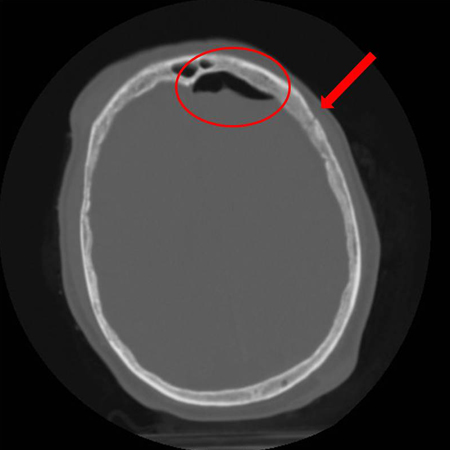

Axial CT scan demonstrating open elevated linear skull fracture (large arrow). Note the air in the soft tissues (small arrow), the small amount of pneumocephalus associated with the fracture (circle), and that the level of elevation of the bone fragment is significantly more than the thickness of the bony table

From the teaching collection of Demetrios Demetriades; used with permission

Axial CT scan demonstrating an open nondepressed linear skull fracture (arrow) associated with pneumocephalus (circle)